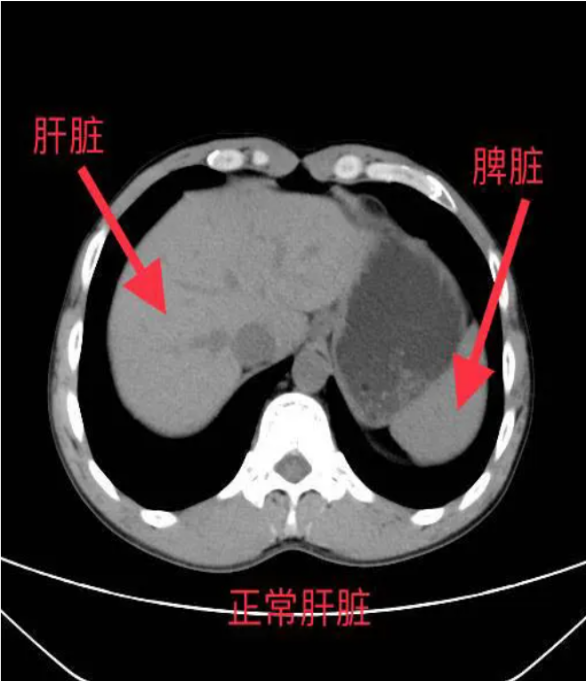

*肝脏密度降低:脂肪的CT值低于正常肝组织,因此脂肪肝在CT图像上表现为肝脏密度普遍降低,与脾脏密度相比更加明显。

*肝脾CT值比值:正常情况下,肝脏CT值高于脾脏,而脂肪肝患者的肝脾CT值比值会降低,甚至出现反转。